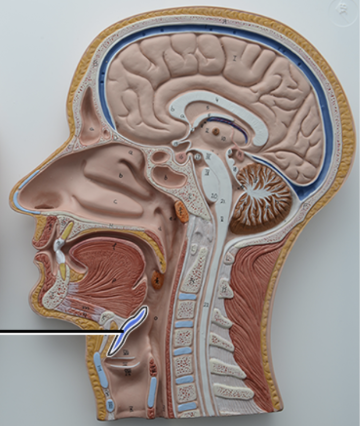

Nasal cavity

What structure is this?

Superior Nasal Concha

What structure is this?

Middle Nasal Concha

What structure is this?

Inferior Nasal Concha

What structure is this?

The nasopharynx region of the pharynx

What structure is this?

The Oropharynx region of the pharynx

What structure is this?

The Laryngopharynx region of the pharynx

The pharynx

What structure is this?

Nasal Septum